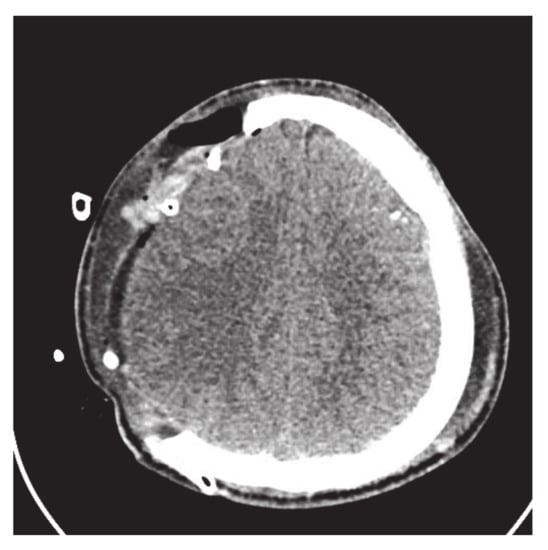

Figure 10. Parietal bone fracture.

This subsection addresses the critical analysis of different schemes based on Bézier-like functions such as G C 2 , G C 1 , C 1 rational cubic Ball curves, NURBS curves and B-spline curve of degree three. Different types of fractures have been constructed using CT scan, such as in Figure 10. Initially, the C 1 rational cubic Ball curve is used to construct the boundary curve of the fractured part, as shown in Figure 11. This scheme works well for small fractures but it reduces the smoothness and flexibility when the defected part become bigger and irregular, as shown in Figure 12 and Figure 13. However, the results obtained by G C 1 , G C 2 rational cubic Ball curves are better, smoother and more flexible than the C 1 rational cubic Ball curve due to the presence of more shape parameters, as shown in Figure 14. The comparison of all curves is shown in Figure 15. In this figure, the red curve is obtained using the G C 1 rational Ball, the blue and green curves are obtained using the C 1 rational Ball.